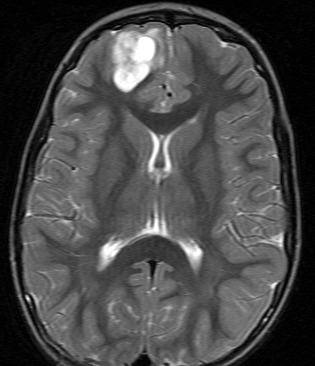

- 大脳にもさまざまな神経膠腫ができます

- 膠芽腫のように悪性度の高いものや乏突起膠腫のように治るものもあります

小児にできた右前頭葉の乏突起膠腫グレード2です。右は術後の写真で,手術だけで治りました。